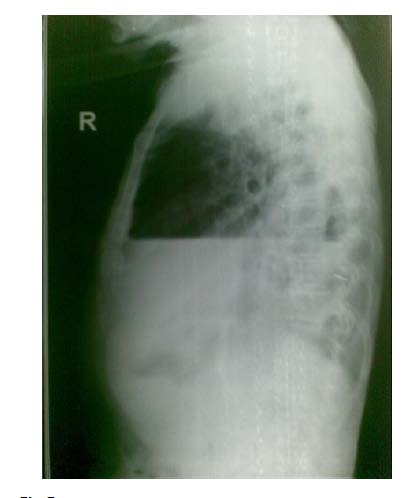

Clinical clue: crepitus in the muscle planes overlying the surgical emphysema. The most obvious finding in this Chest X ray in figure 4 cavity outside the pleura. The hyperlucency is situated lateral to the margin of the collapsed lung (outlined by the visceral pleura). Therefore this hyperlucency is clearly due to presence of free air in the pleural cavity. The simultaneous presence of air and fluid indicated by a horizontal fluid level, helps to identify this situation as a hydropneumothorax. Note that the visible portion of the partially collapsed lung is not healthy-there is an apical cavity. The opposite lung also shows evidence of infiltration. The overall picture strongly suggests possibility of underlying tuberculosis as evidenced by the cavity, whose rupture is most likely the cause of pneumothorax.

There is a clearly seen horizontal fluid level in the lateral view in Figure 5. Above the fluid level there is an area of hyperlucency without lung markings (free air). Margin of the collapsed lung though faintly visible is not seen as clearly as in the PA view.